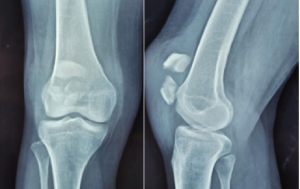

Extreme beak calcaneal fracture (type 2 Lee’s fractures) are relatively rare injuries, accounting for approximately 1.3–3% of all calcaneal fractures. The incidence is highest in elderly particularly in women. This type of fracture requires timely interference and treated as surgical emergency within 6 h to avoid skin necrosis and soft-tissue compromise. Despite their rarity, these fractures can result in significant functional impairment if not promptly managed [1]. They can lead to soft-tissue compromise, chronic pain and alterations in gait mechanics. In addition, non-union or malunion may contribute to the development of subtalar arthritis if there is an intra-articular extension. Several risk factors have been identified for calcaneal tuberosity avulsion fractures. Osteoporosis plays a significant role, especially in elderly patients [2]. Other contributing factors include diabetes mellitus [3-8] and peripheral neuropathy which can affect bone quality and proprioception [9,10]. The calcaneal tuberosity serves as the insertion point for the Achilles tendon, the strongest tendon in the human body. The Achilles tendon originates from the distal end of the triceps surae muscle group (average length of approximately 15 cm) and inserts into the middle third of the posterior surface of calcaneal tuberosity of varying width of 1.2–2.5cm [11,12]. Anatomical studies have shown that in some individuals, the Achilles tendon has an extensive insertion into the calcaneal tuberosity, which may predispose them to avulsion fractures [13]. The overall calcaneus is composed primarily of cancellous bone encapsulated by a relatively thin cortical shell. The density of the trabecular structure determines the overall strength of the calcaneus and the calcaneal tuberosity. In patients with osteoporosis or other conditions affecting bone quality, the decreased trabecular density can increase the risk of avulsion fractures. The mechanism of injury typically involves a sudden, strong contraction of the gastrocnemius-soleus complex, often with the ankle in a dorsiflexed position. This creates a tensile force through the Achilles tendon that can exceed the strength of the bone at its insertion, resulting in an avulsion fracture [14-17]. Combined with the above anatomy, a more extensive insertion of the Achilles tendon at the calcaneal tuberosity will lead to a more vertical direction of force and even avulsion fractures. Collectively, the distraction force generated by the Achilles tendon at the calcaneal tuberosity and the trabecular density of the calcaneus will play a major role in the occurrence of fractures. Several classification systems have been proposed for calcaneal tuberosity avulsion fractures. The Lee classification [18], which is widely used, describes four types of fractures: Type I: Simple extra-articular avulsion fracture (sleeve fracture) Type II: Beak fracture with a large fragment Type III: Infrabursal avulsion fracture from the middle third of the posterior tuberosity Type IV: Beak fracture with a small triangular fragment (Fig. 1). More recently, the Carnero Martín de Soto classification has been introduced, which focuses on fracture displacement as a predictor of complications. This system classifies fractures as Type 1 (displacement <2 cm) or Type 2 (displacement ≥2 cm), with Type 2 fractures associated with a higher risk of soft-tissue complications. While conservative management is limited to only undisplaced fracture, surgical intervention is mandatory for displaced fractures or those involving a large portion of the calcaneal tuberosity. Various surgical techniques have been described, including closed reduction and internal fixation (CRIF) with cannulated cancellous (CC) screw fixation, open reduction and internal fixation with plates and screws, tension band wiring, suture anchor suture bridge techniques, side-locking loop suture (SLLS) techniques, etc. The use of CC screws for the fixation of calcaneal tuberosity avulsion fractures has gained popularity due to its ease of application and promising results. This technique offers several potential advantages, including minimal soft-tissue dissection, strong interfragmentary compression and early mobilization. The primary aim of this prospective study was to evaluate the functional outcomes of extreme beak calcaneal fractures – Type 2 Lee’s tuberosity avulsion fractures. Although multiple case reports are documented, there is a limited literature support specifically evaluating the outcomes of CC screw fixation focusing on such fractures (Type 2 Lee) in larger samples. Secondary objectives included assessing the rate of complications, time to fracture union and return to pre-injury activities.

A 38-year-old male presented with right heel pain following a fall from a ladder. Radiographs and X-ray revealed a displaced extra-articular calcaneal extreme beak fracture Lee Type 2. The patient underwent emergency early CRIF with CC screw fixation as described with trauma to surgery interval 5 h. At 12-month follow-up, the patient had an AOFAS score of 94, with complete return to pre-injury activities and no pain (Fig. 2).